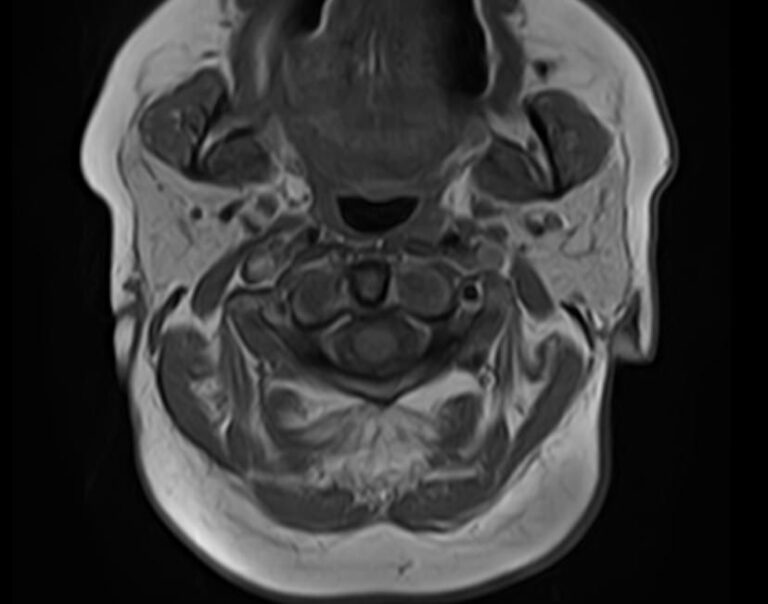

Магнитно-резонансная томография на сегодняшний день является наиболее информативным исследованием слюнных желез. Метод позволяет получить изображения мягкотканных структур с высокой детализацией, при этом отсутствие вредного ионизирующего излучения обеспечивает безопасность процедуры и позволяет проводить ее неоднократно по мере необходимости. Это бывает важно для оценки эффективности проводимого лечения.

В нашей клинике МРТ слюнных желез выполняется на высокопольном томографе экспертного класса TOSHIBA VANTAGE TITAN 1,5 Тесла. Аппарат производит сканирование в трех различных плоскостях в виде тончайших послойных срезов с шагом от 1 мм. Высокая индукция магнитного поля, используемая в аппарате, обеспечивает превосходное качество изображений. Кроме того, с помощью инновационных компьютерных приложений реконструируются объемные изображения исследуемой зоны, что улучшает визуализацию и повышает точность и достоверность диагностики.